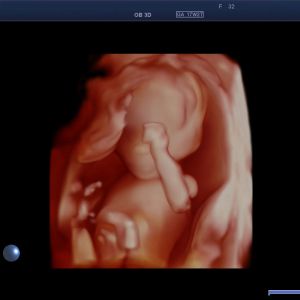

Früher Fehlbildungsultraschall / Ersttrimesterdiagnostik

Viele schwerwiegende komplexe Fehlbildungen können bereits früh erkannt werden. Ein unauffälliger Befund kann somit zu einer deutlichen Reduktion von Sorgen und Ängsten beitragen. Bei auffälligem Ultraschallbefund kann eine weiterführende Diagnostik zeitnah erfolgen.